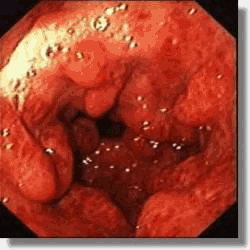

As alterações da gastropatia hipertensiva portal são mais evidentes na mucosa do corpo e fundo do estômago. Os aspectos endoscópicos incluem um padrão de eritema fino, difuso e pontilhado, rash escarlatiniforme ou o padrão conhecido como “pele de cobra” ou “mosaico”, onde se observa áreas avermelhadas, pequenas e poligonais delimitadas por bordas deprimidas e amarelo claras5-8. A gastropatia severa é caracterizada pela presença de pontos vermelho escuros ( “cherry red spots” ) e áreas de hemorragia mucosa difusa ( “gastrite hemorrágica” )5,8. Em estudos endoscópicos com grande amostragem de cirróticos assintomáticos, mais que 50 % apresentam sinais de gastropatia hipertensiva portal, sendo o achado mais comum o padrão mosaico ou em pele de cobra no estômago proximal8,9.

Em 1994, o NIEC (New Italian Endoscopic Club) propôs nova classificação para padronizar as descrições da gastropatia hipertensiva portal10. A classificação se baseia em 4 sinais endoscópicos elementares (tabela 2).

| Classificação da gastropatia hipertensiva portal (Milão –1994) |

| 1. Padrão mosaico ( mosaic-like pattern – MLP ), graduado como leve, moderado ou severo |

| 2. Marcas vermelhas ( red marks – RM ), que incluem lesões puntiformes vermelhas ( red point lesions – RPL ) e pontos vermelho cereja ( cherry red spots – CRS ) |

| 3. Pontos marrom escuros ( black Brown spots – BBS ) |

TRATAMENTO